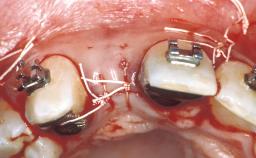

Surgical SAC Modifiers

| Periodontal Status | - |

|---|

Prosthodontic SAC Modifiers

| Soft Tissue Contour and Volume | - |

General SAC Modifiers

| Oral Hygiene and Compliance | - |

|---|---|

| Access | - |

| Craniofacial/Skeletal Growth | - |